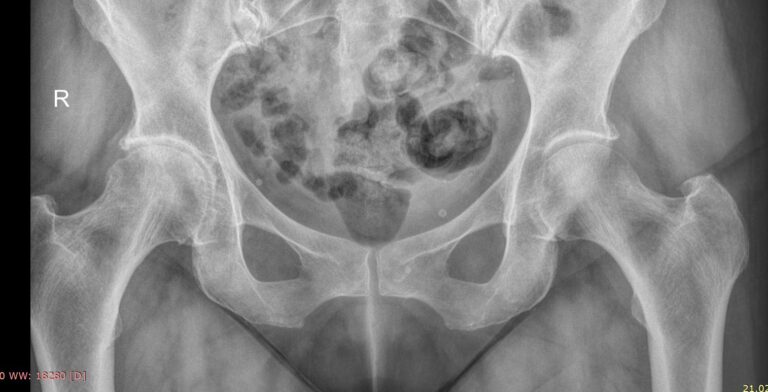

Рентгеновское исследование ― классический метод диагностики костно-суставных патологий. Он основан на способности ионизирующего излучения проходить сквозь ткани и поглощаться ими в большей или меньшей степени. Кости, как наиболее плотные в организме, поглощают большее количество излучения и на классическом негативном снимке выглядят светлыми образованиями. Видны и все изменения в костях и окружающих их структурах.

Рентгеновское исследование в 2 проекциях ― прямой и по Лаунштейну ― входит в список обязательных диагностических процедур при многих болезнях, поражающих тазобедренный сустав. Снимки необходимы как для подбора терапевтического лечения, так и для планирования оперативного вмешательства при эндопротезировании.

Что показывает рентген тазобедренных суставов в прямой проекции и по Лаунштейну

• Контуры костей суставов, линии переломов;

• Соответствие сочленяющихся поверхностей;

• Суставную щель и ее особенности;

• Состояние костной ткани, очаги разрежения;

• Новообразования;

• В положении Лаунштейна особенно четко видна головка бедренной кости и ее изменения.